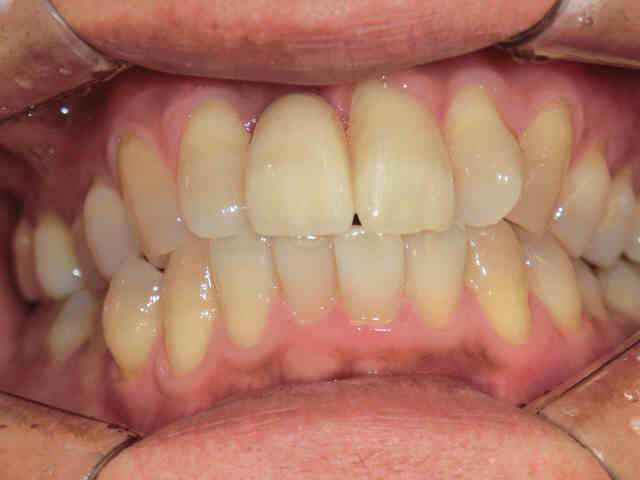

インプラント症例紹介(40代男性/右上前歯)

初診時、右上前歯がグラグラしており、抜歯およびインプラント治療をご希望されました。診査の結果、歯根が骨にほとんど埋まっておらず、保存は困難であったため、抜歯を行いました。

抜歯後は骨の幅が不足していたため、骨造成(GBR)を併用し、約半年後にインプラント治療を行いました。

治療に使用したかぶせ物(人工歯)はオールセラミック製で、自然な透明感があり、変色しにくい素材です。また、清掃性が高いとされており、プラーク(歯垢)が付きにくい特徴があります。